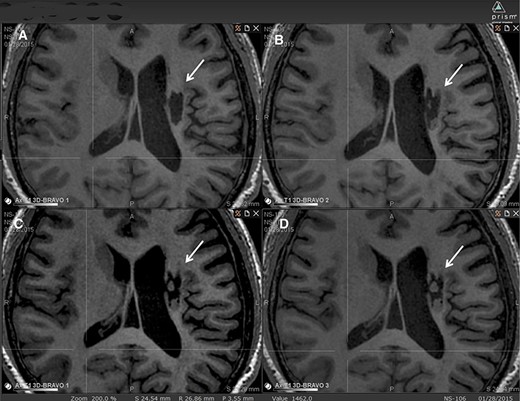

图中显示了B组 (#106) 受试者在T1MRI上随时间的变化。

(A):基线时,(B) 6个月随访时,(C) 12个月随访时,(D) 24个月随访时。箭头表示梗塞腔。

可以看到两个组织团块,在基线时不存在,推测是来自植入的NSI-566,随着时间的推移,它们似乎慢慢填满了腔体。